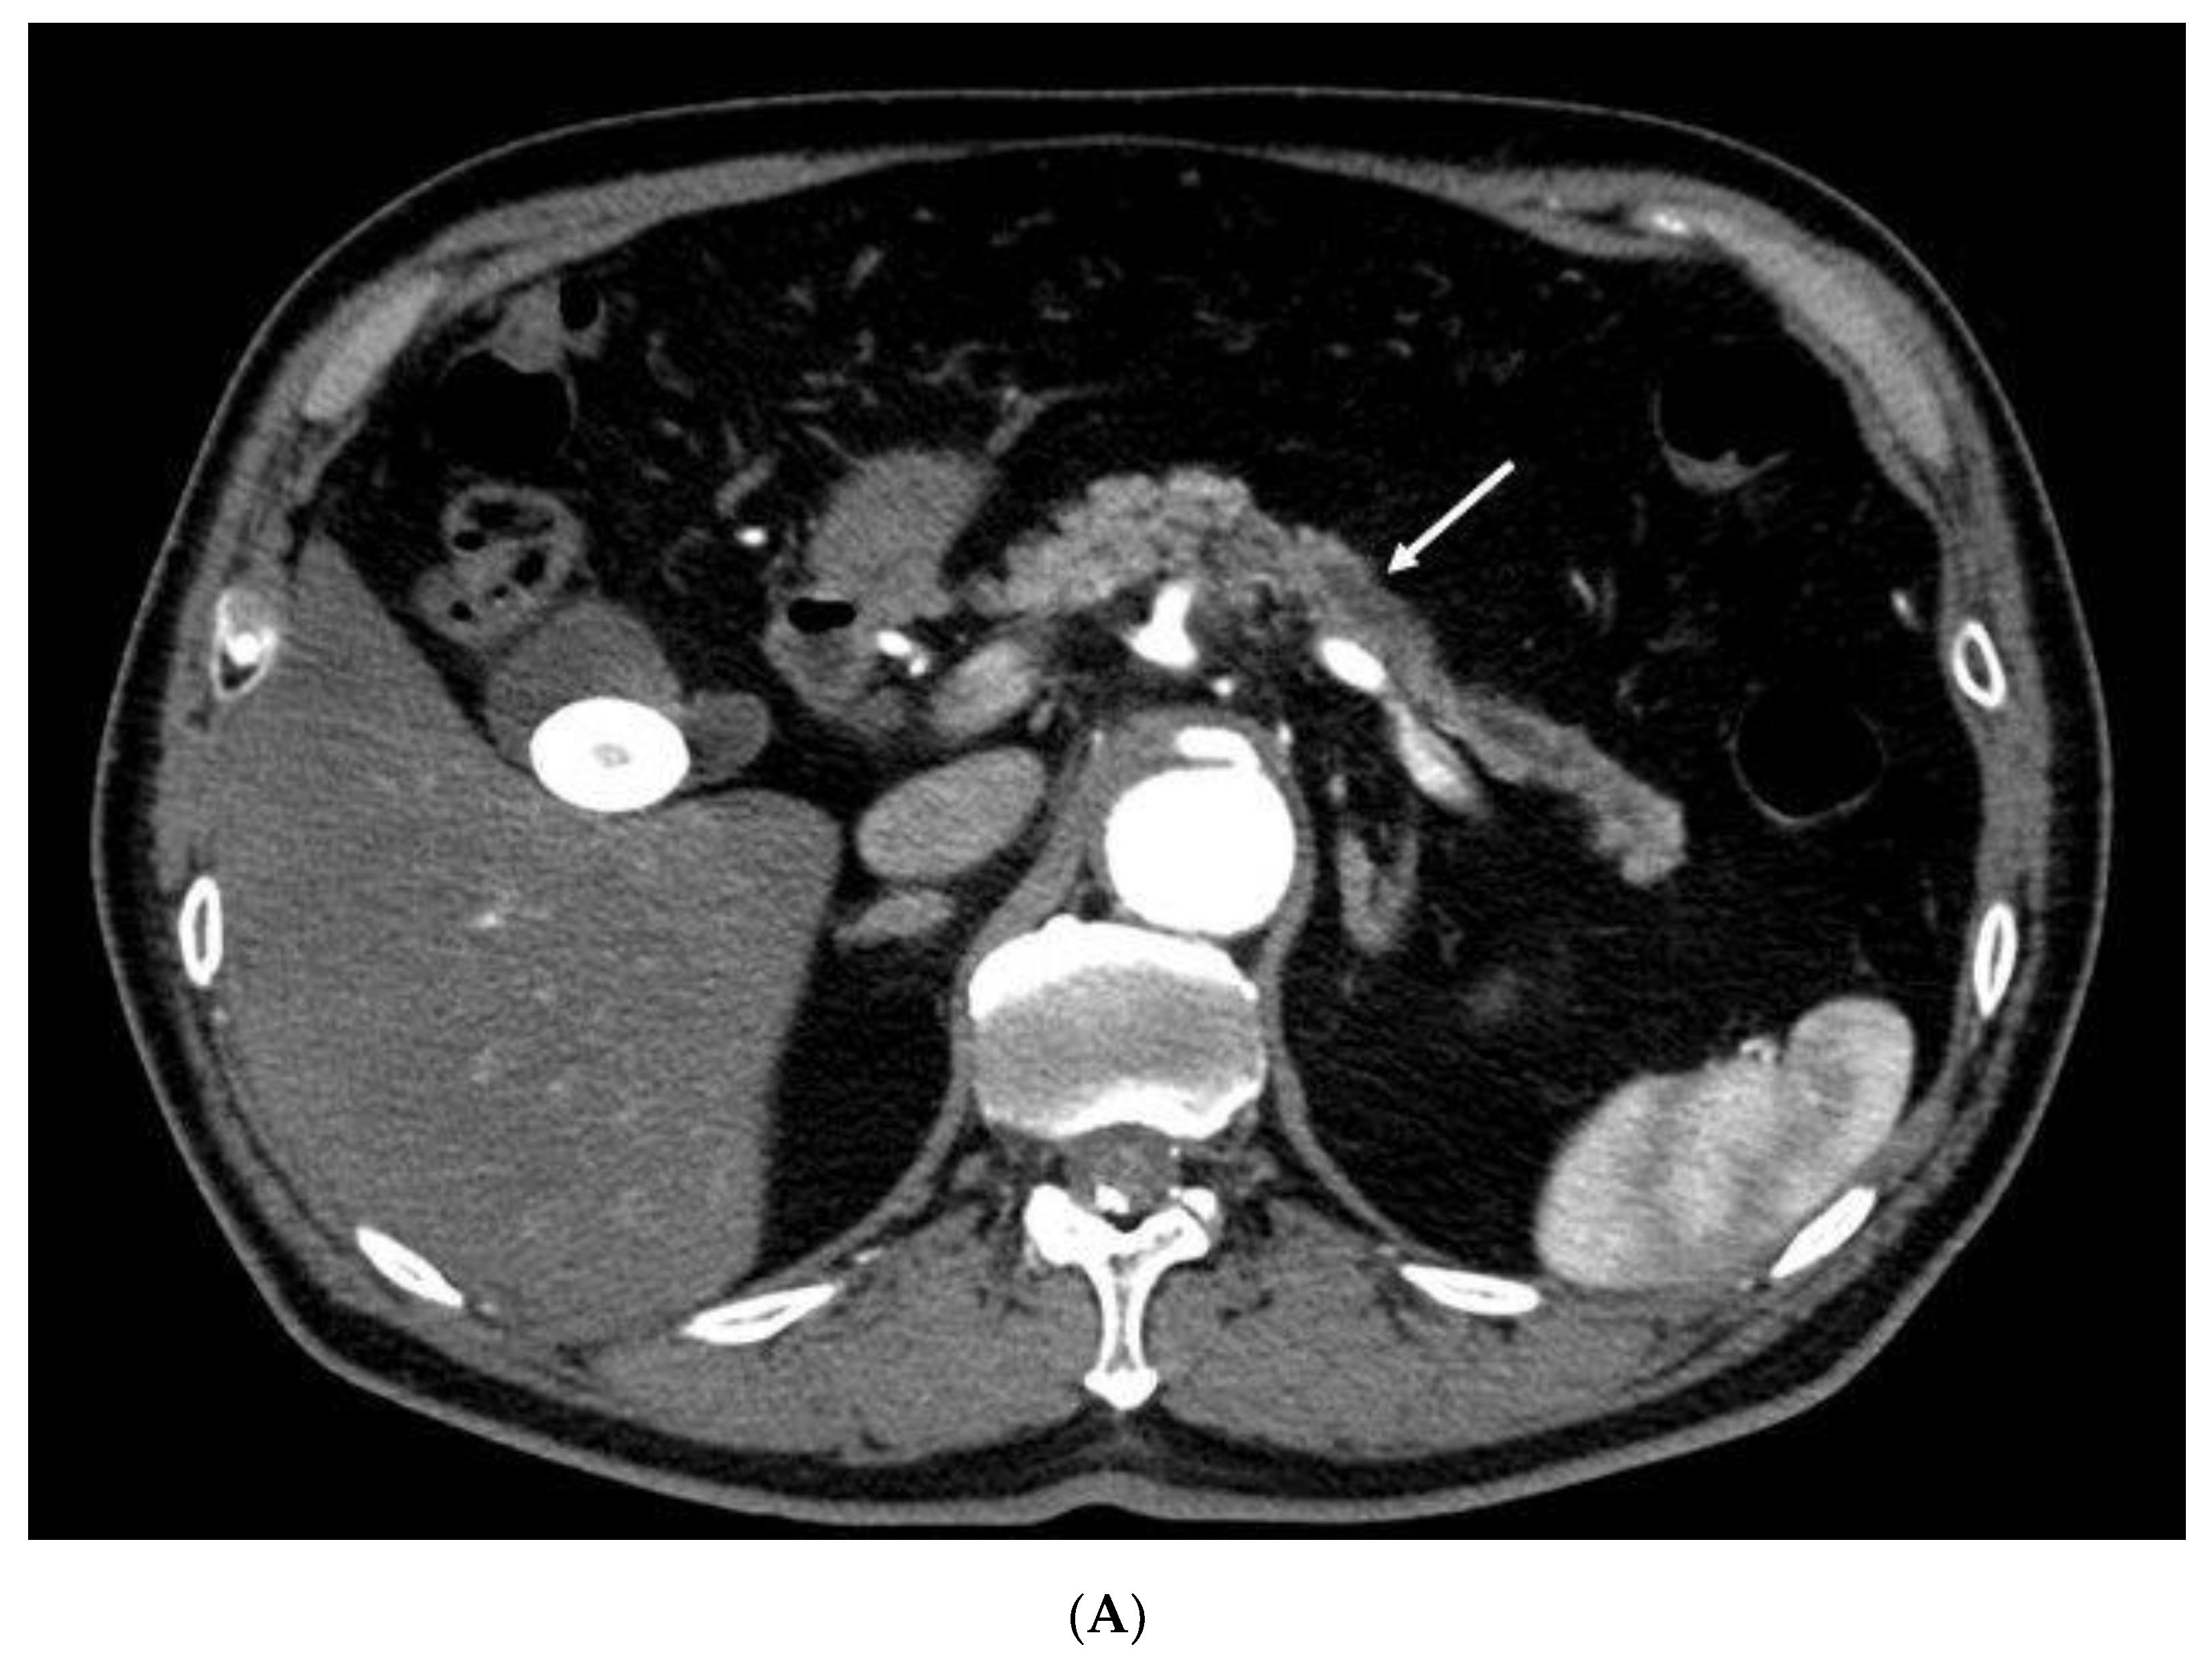

Utility of Contrast-Enhanced Harmonic Endoscopic Ultrasonography for Early Diagnosis of Small Pancreatic Cancer